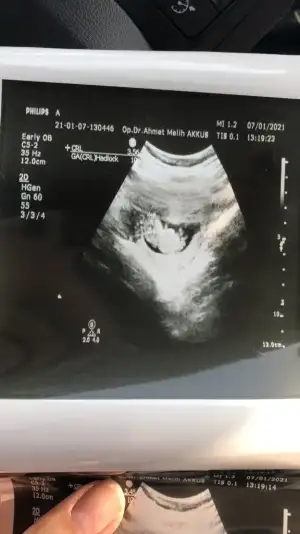

Ikra meyra Ikra meyra canım bu da benım bebeğim evet pek net değil ama bakar mısın 11+2

Eklentiler

• IMG_20210115_111711.webp

IMG_20210115_111711.webp

28,5 KB · Görüntüleme: 79